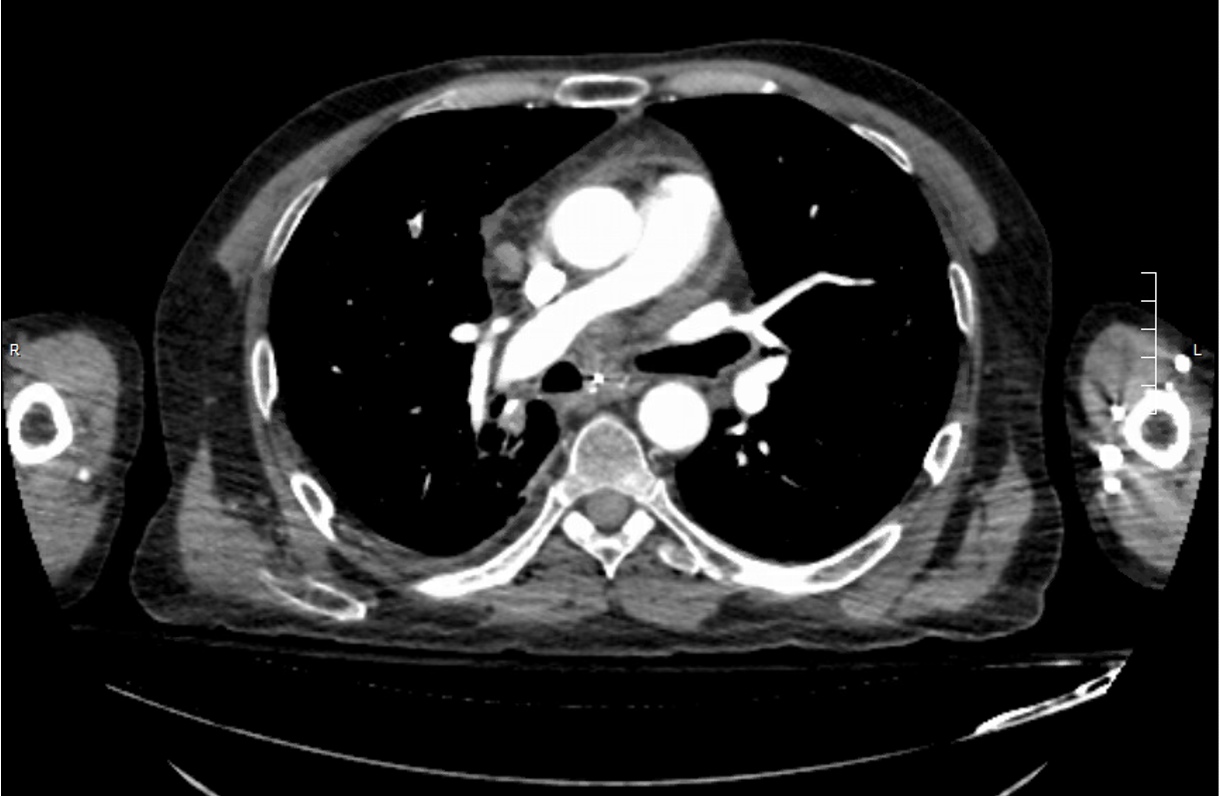

The patient’s history of cancer and associated high suspicion for pulmonary embolism prompted computed tomography (CT) pulmonary angiography, the results of which revealed an acute right upper lobe segmental pulmonary embolus (Figure 2). A small to moderate sized pericardial effusion was also noted (Figure 3).

Figure 2. CT pulmonary angiography showing a small filling defect.